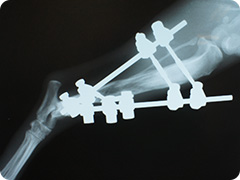

- 骨折

- 高いところから飛び降りたりすることで骨折することがあります。骨折した足はぶらーんとして床に足を付けられない状態になります。

創外固定法による治療

プレートを用いた治療